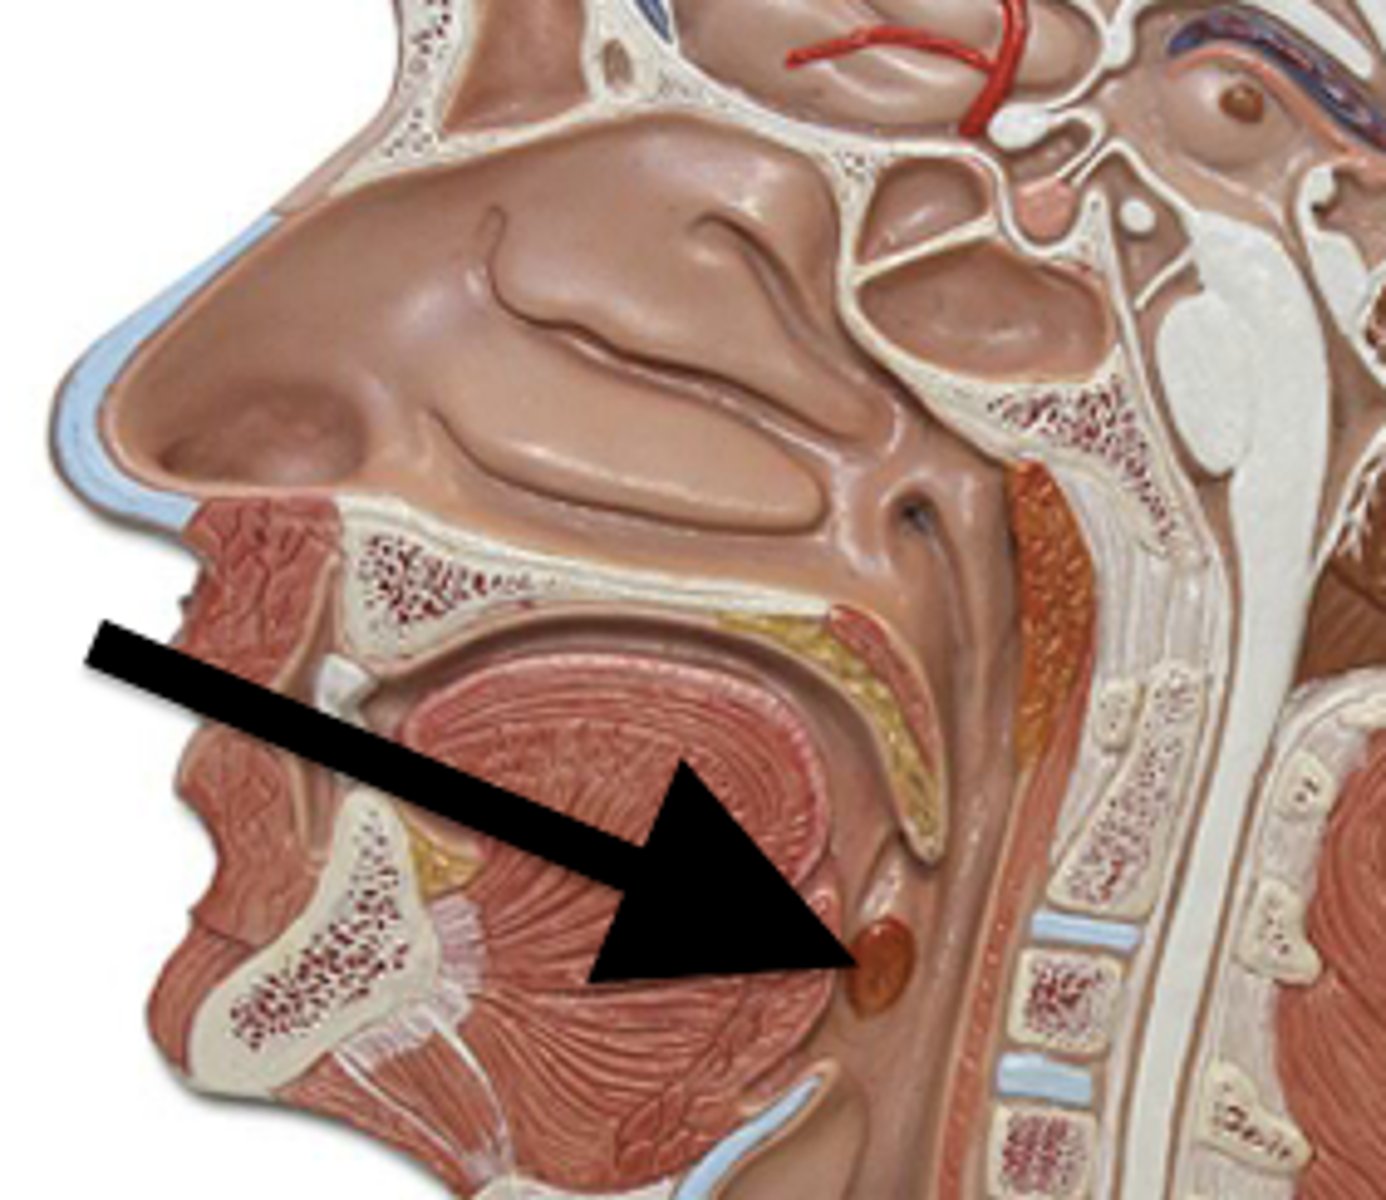

Nose

Organ of smell

Bridge

Tip

Ala

Nares

Columella

Vestibule

Nasal Cavity

Hollow space behind the nose

Turbinates (Conchae)

- Bones that protrude into the nasal cavity- that increases surface area for filtering dust and dirt particles by the mucous membrane

- There's an inferior, middle, and superior one (2.), 3.), 4.))

Olfactory Region

A dime-sized area at the top of each nasal cavity that houses sensors responsible for smell (1.))

Hard (Bony) Palate

Anterior palate portion that is supported by the palatine processes of the maxillae and the palatine bones (8.))

Meatuses

- Constricted passageways in the nasal cavity that produce air turbulence

- There's an inferior, middle, and superior one

(5.), 6.), 7.))

Soft Palate

Posterior palate portion, not supported by bone (9.))

Oral Cavity

Mouth

Uvula

Pharynx (Throat)

Passageway for air, leads to trachea

Nasopharyx

The portion of the pharynx that extends from the nostrils to the soft palate

Oropharynx

Central portion of the pharynx between the roof of the mouth and the upper edge of the epiglottis

Tonsils

Masses of lymphatic tissue in the back of the oropharynx

3 Tonsils in the Mouth

- Palatine

- Adenoid

- Lingual

Palatine Tonsil

One of a pair of almond-shaped masses of lymphatic tissue in the oropharynx

Adenoid Tonsil

Pharyngeal tonsil

Lingual Tonsil

Tonsil located at the base of tongue